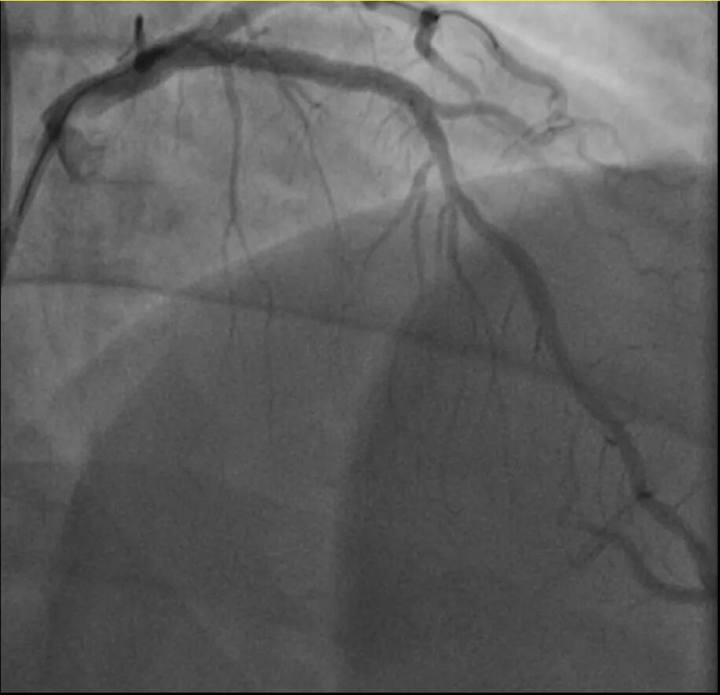

介入治疗前后影像图

他的血糖一直偏高,服药后控制不佳,但年轻的钱先生并没有太上心。周末,他和孩子爬了一座山,隔天,钱先生就因突发胸骨中段压榨性疼痛被送到了急诊,最后被证实也是心梗——心脏三支主要血管之一回旋支远段次全闭塞。

浙江医院心血管内科翁莹政医师介绍,这位患者来院时血糖12.79mmol/L(正常空腹值应该在3.9~6.1mmol/L),甘油三酯也超标。“三高”(高血压、高血脂、高血糖)是导致动脉粥样硬化(包括心脏的冠状动脉)的主要危险因素,在冠状动脉粥样硬化早期,血管狭窄可能并不严重,仅当血管狭窄到一定程度时,在运动、情绪激动等情况下,心肌耗氧量增加,就可能造成心梗等急性心肌缺血事件。所幸经过汤益民团队的及时介入治疗,钱先生也转危为安。